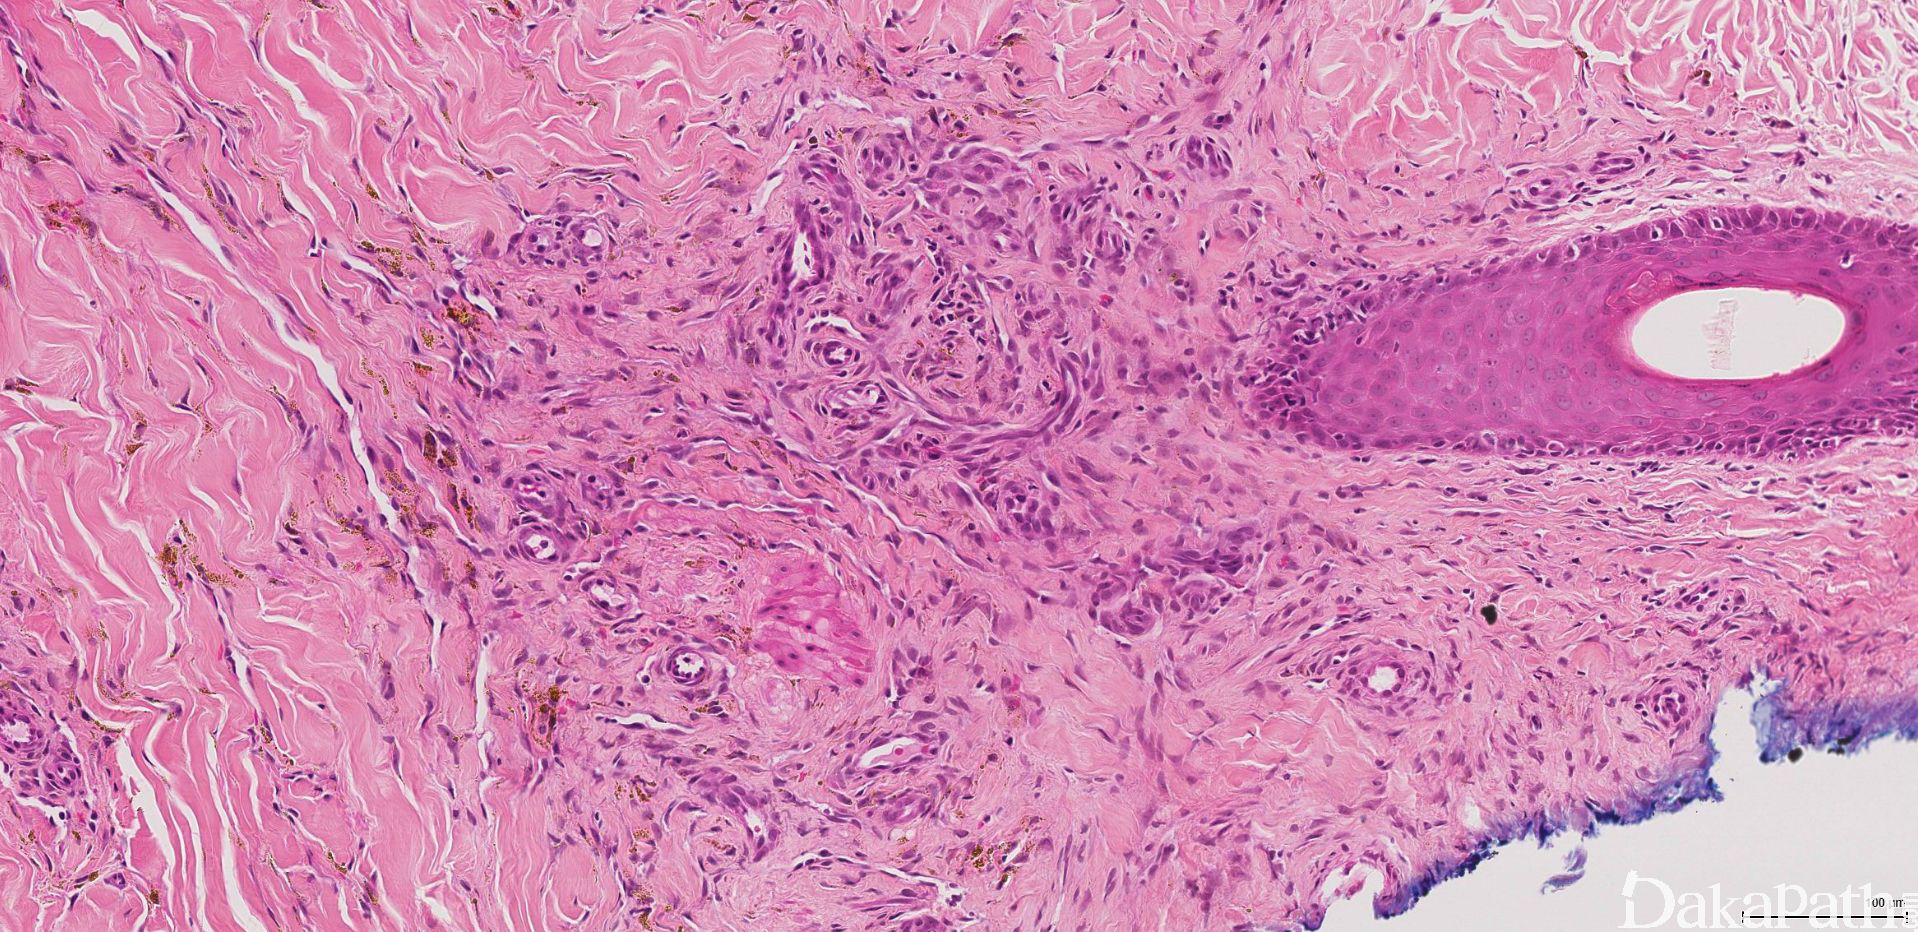

II 期为斑点(斑片)期:变化极似肉芽组织,真皮血管数量增加,形状不规则,在真皮浅层胶原纤维间呈疏松、参差不齐的分支状排列,将真皮胶原纤维分隔。血管周梭形细胞增生、红细胞外渗,间质中淋巴细胞、浆细胞浸润,伴含铁血黄素沉着。

III 期为斑块期:皮肤轻度隆起,病变累及真皮全层或累及皮下组织。与 II 期形态学有明显的重叠,血管增生更广泛,红细胞外渗和含铁血黄素沉着更显著。管腔轮廓呈锯齿状,真皮血管周围嗜酸性梭形细胞增多,炎细胞浸润明显,可见大量的红细胞外渗,含铁血黄素及玻璃样小体。